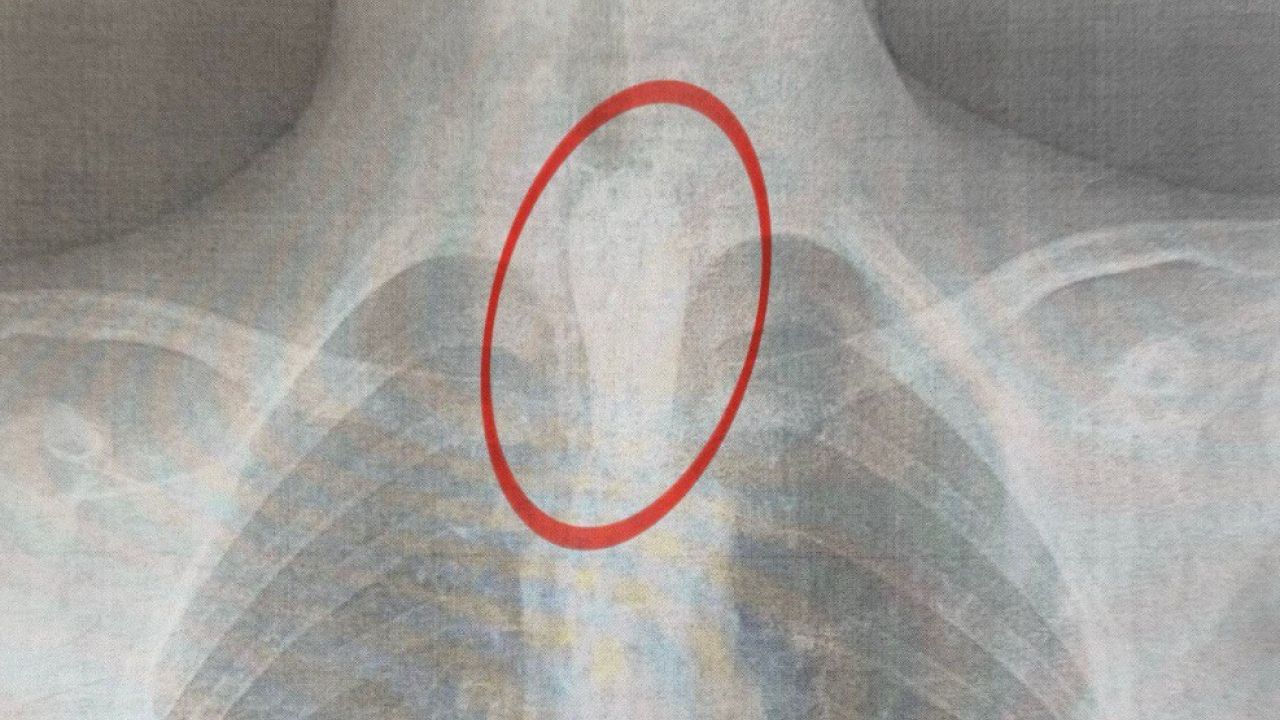

"Стравохід має природні звуження: на рівні шиї, біля аорти та на вході до шлунка. У цьому випадку шматок м'яса зупинився на другому звуженні. Слина постійно виробляється, але не може пройти далі, що викликає сильну слинотечу, відчуття стороннього тіла за грудиною і страх. Дитина не могла нормально дихати", – розповів торакальний хірург нашого Центру Олександр Колодій (Олександр Колодій).

Операцію провели вночі – о 2:00 хлопця терміново доправили до операційної, де команда фахівців виконала ригідну езофагоскопію. Втручання тривало близько години: великий шматок м’яса видаляли поетапно, щоб не пошкодити стінки стравоходу.